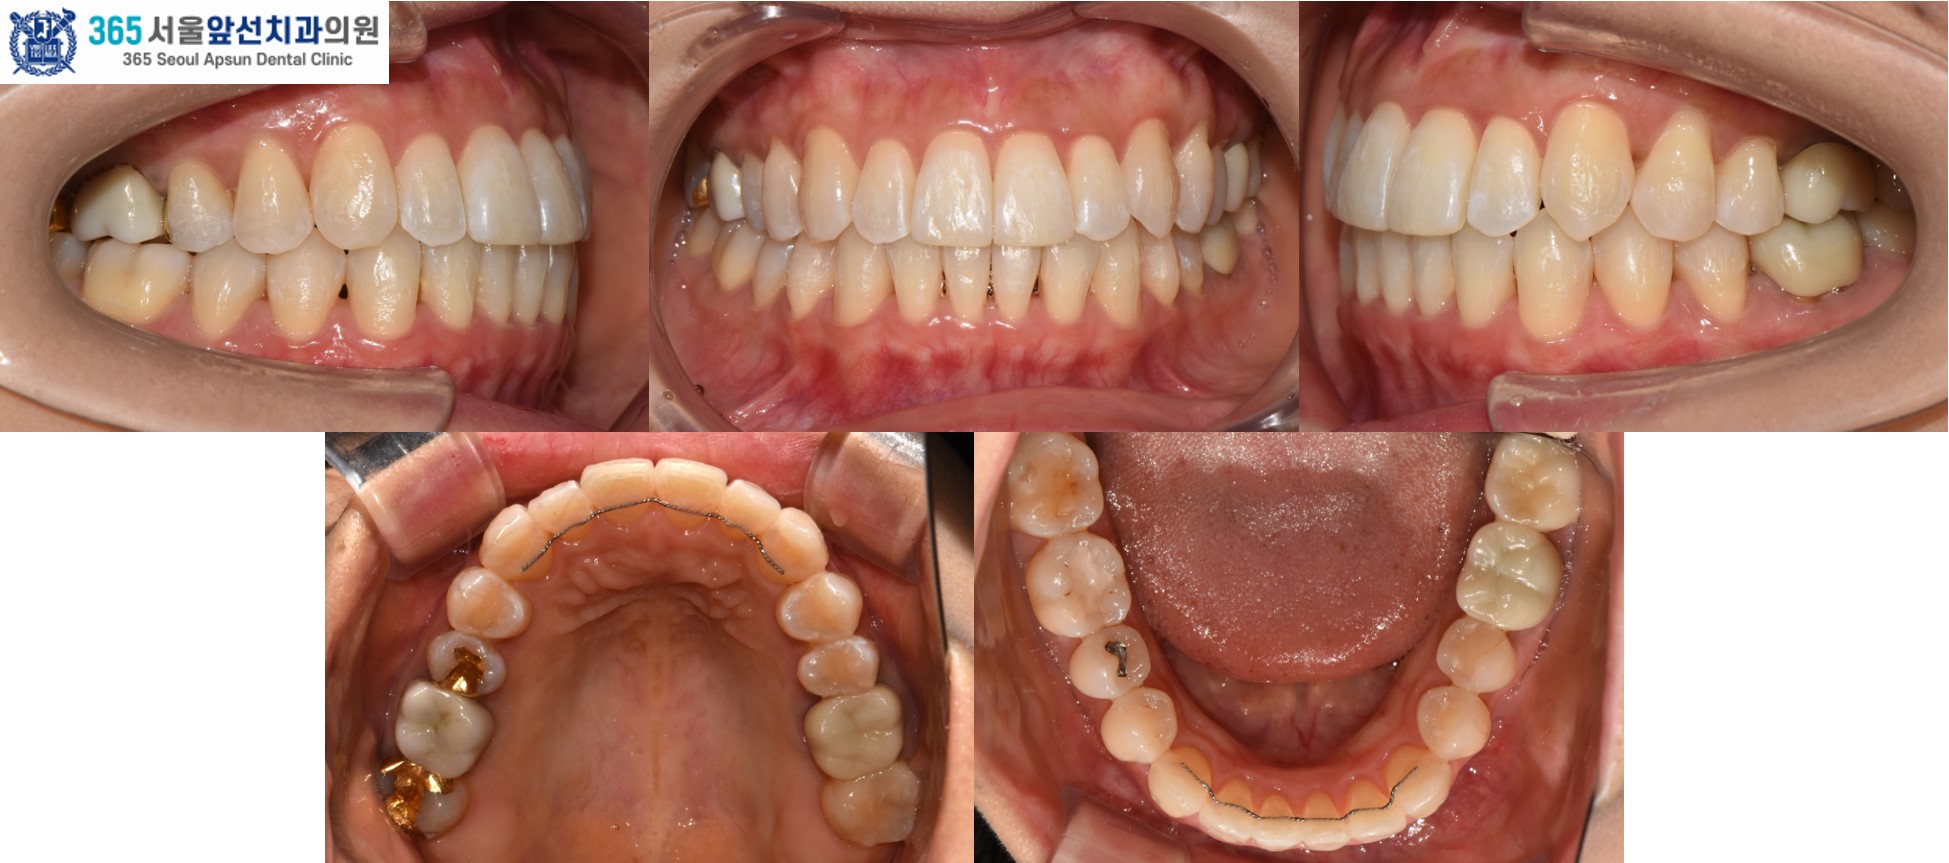

촬영일시 : 2025.12.16. 3월 12일 치료를 개시하여 12월 16일에 교정치료를 종료하였으며 총 9개월의 치료기간이 소요되었습니다. 치열이 가지런하게 배열되었고 목표하였던 견치의 1급 관계 회복, 앞니의 수평 피개 감소, 정중선 불일치 개선이 완료되었습니다. 환자분께서 치료를 열심히 따라와주셔서 치료가 깔끔하게 잘 마무리되었습니다. ![]() 촬영일시 : 2024.11.26. / 2025.12.16. 촬영일시 : 2024.11.26. / 2025.12.16. 투명교정이 기존의 부착식 교정장치보다 효과가 떨어지지는 않는지 여쭤보시는 환자분들이 종종 계십니다. 투명교정으로도 이상적인 치료 결과를 낼 수 있다는 예로 본 증례를 소개드렸습니다. 투명교정치료는 하루 20시간 이상의 착용이 필요하여 환자와 의료진이 함께 만들어가는 치료입니다. 부착식 장치에 비하여 위생 관리가 용이하며 협점막이 편안하고 심미적입니다. 감사합니다!

[ 치료기간: 2024년 11월26일 ~2025년 12월 18일 ] ※ 365서울앞선치과의원의 모든 컬럼은 각 진료과 의료진이 직접 작성합니다. 365서울앞선치과의원 임상 케이스 게시물은 환자분께 의학적으로 정확하고 상세한 정보를 드리기 위해 각 진료과 의료진이 직접 작성하며, 모든 증례 사진은 본원 의료진이 직접 시술한 증례를 촬영한 것으로, 의료법 제23조, 제56조에 의거하며 환자분의 동의를 얻어 포스팅에 사용하였습니다. 또한 해당 케이스는 본 환자분의 치료 결과이며, 환자 상태에 따라 치료의 결과는 달라질 수 있습니다. |